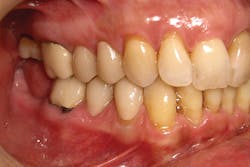

Lastly, the intaglio of the crowns was treated with hydrofluoric acid and silane as described above, and definitive cementation was accomplished using Prime&Bond Elect and Calibra Ceram. Final occlusion and interproximal contacts were checked, and the patient was released after receiving four individual crown restorations all completed in one visit (figures 6 and 7).

Figure 6: Final Celtra Duo restorations on teeth Nos. 4, 5, 28, 29 on 34-year-old female patient.